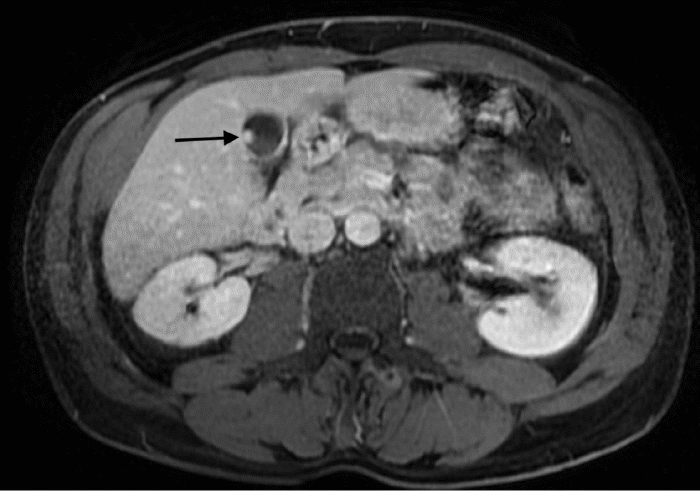

Clinically, the patient reported intermittent abdominal pain, which notably did not worsen postprandially. He denied any history of cholelithiasis, nausea, vomiting, diarrhea, melena, hematochezia, jaundice, or significant weight loss. His social history was significant for daily consumption of three to four cigars and previous heavy alcohol use (12 to 14 drinks per week). Physical examination findings were unremarkable, and laboratory investigations revealed no abnormalities. Based on the patient's symptomatology and the identified gallbladder mass, further diagnostic evaluation with magnetic resonance imaging (MRI) with and without contrast, supplemented by magnetic resonance cholangiopancreatography (MRCP), was pursued one month later. Multiplanar, multisequence MRI demonstrated an 8-millimeter, non-calcified, soft-tissue mass arising from the anterior gallbladder wall, consistent in appearance with a polyp. (Figure 1 and Figure 2). T2-weighted imaging confirmed this finding and also identified small superiorly located gallstones without overt gallbladder wall thickening. The MRCP component of the study yielded unremarkable findings regarding the biliary tree.

Figure 1. MRI without contrast with MRCP. Published with Permission

Figure 2. MRI with contrast with MRCP. Findings: Non-calcified soft tissue mass arising from the anterior wall of the gallbladder. Published with Permission